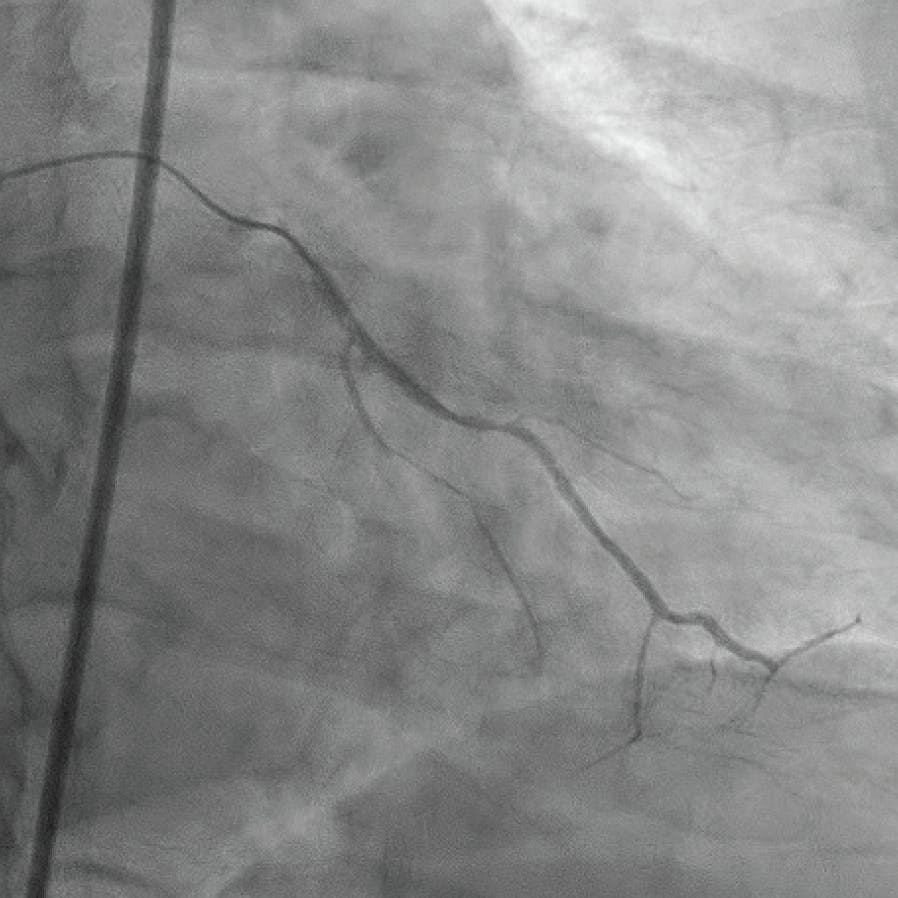

A man in his late 50s with a medical history of hypertension and type 2 diabetes was transferred from an outside facility with a non–ST-segment elevation myocardial infarction. His initial troponin I was 4.067 ng/mL with a peak of 15.783 ng/mL. The initial electrocardiogram demonstrated normal sinus rhythm with symmetric inferolateral T wave inversion. He reported intermittent chest pain for 2 weeks prior to arrival, with severe chest pain the day of presentation to the outside facility. Diagnostic cardiac catheterization revealed a subacute occlusion of the proximal circumflex and a proximal CTO of the dominant RCA with a collateral network primarily via the patent left anterior descending (LAD) artery system (Figure 2). The left ventricular ejection fraction was globally mildly depressed at 40% with inferobasal hypokinesis. The echocardiogram confirmed an ejection fraction of 40% and no significant valvular dysfunction. Consideration was given to surgical versus percutaneous options, and given the patient’s persistent unstable ischemic symptoms, a percutaneous option was pursued.

Figure 2. LAD with a collateral network to the RCA system.